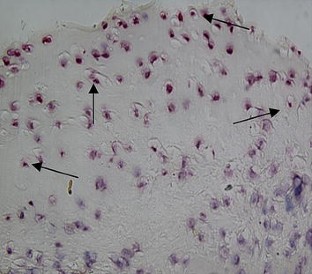

Observe pulse electromagnetic fields (PEMFs) effects on ovariectomized (OVX) rats, to study the mechanisms of PEMFs therapy for postmenopausal osteoarthritis. Forty-eight female rats were exposed to PEMFs (PEMFs group), administrated E2 and placebo PEMFs (E group), or were treated with placebo PEMFs (OVX and Sham groups). The treatment duration was 30 days after which serum E2 levels, chondrocyte morphology, chondrocyte apoptosis and matrix metalloproteinases-13 expression in knee joint was analyzed. We observed differential chondrocyte formation in each group, and serum E2 content in the PEMFs and E group were significantly higher than the OVX group. The apoptosis index of chondrocytes and the positive index of MMP13 expression in the PEMFs group and E group were significantly lower than the OVX group. PEMFs has a systemic effect on estrogen metabolism in ovariectomized rats, then inhibit chondrocyte apoptosis and downregulate MMP13 expression of knee joint cartilage. It may be the mechanisms by which PEMFs therapy works for on postmenopausal osteoarthritis.

Fig. 1

Fig. 2

Fig. 3

Fig. 4

Fig. 5

Fig. 6

Fig. 7

Fig. 8

Fig. 9

Fig. 10

Fig. 11

Fig. 12